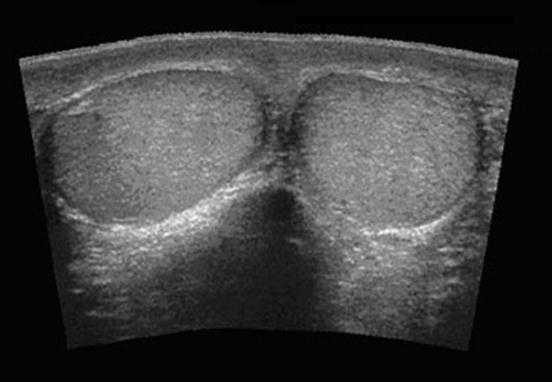

Оба яичка обследуются во время УЗИ как в продольной, так и поперечной плоскостях. Начальное изображение должно захватывать оба яичка, что позволит сравнить между собой их размер и гомогенность, выявить несимметричность, если таковая есть. Далее каждое яичко обследуется в поперечной плоскости от верхнего конца до нижнего. Во время обследования доктор может сохранять изображения и распечатывать их после окончания процедуры. Также врач осмотрит яички и в продольном направлении.

В норме яичко определяется как гомогенная структура овальной формы, эхогенность которой сравнима с эхогенностью щитовидной железы.

На первой картинке визуализируется гомогенная структура яичка в продольной плоскости. Текстура яичка такая же, как у щитовидной железы, представленной на втором изображении.